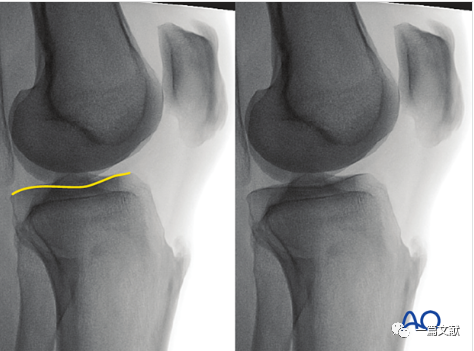

2)标准侧位的评估:1、股骨髁在图像的前方、后方、远端均重叠2、股骨髁位于图像中央 3,C臂机射线平行于胫骨关节面照射。如下图:

3)解剖标志的识别:如下图:1、外侧平台关节面(凸面)2、内侧平台关节面(凹面)3、髁间脊4、胫骨结节5、闭合的骨骺线

4)标准侧位的意义:1、评估内侧和外侧平台复位情况;2、评估胫骨髁间脊复位情况;3、评估胫骨平台是否存在相对于股骨向前或向后的半脱位(表明交叉韧带损伤);4、检视是否存在突入关节的内植物。